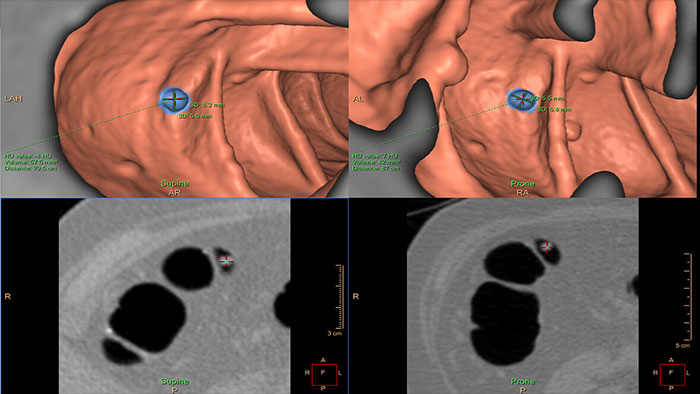

Lung Nodule Assessment (LNA)

CT Lung Nodule Assessment (LNA)

Assessing lung nodules over time

Enables review and analysis of thoracic CT images, providing segmentation, quantification and characterization of physician-indicated lung nodules. The application can be used in both diagnostic and screening evaluations, supporting Low Dose CT Lung Cancer Screening*

• Automatic lung and lobes segmentation and one click 2D and 3D nodule segmentation.

• Supports LungRADS categorization, Fleischner Society guidelines for incidental findings as well as a Risk Calculator tool**.

• Pre-filled data including characteristics for each nodule in configurable presets are provided automatically by the application.

• Lung and nodule segmentations can be shared as RT Structures.